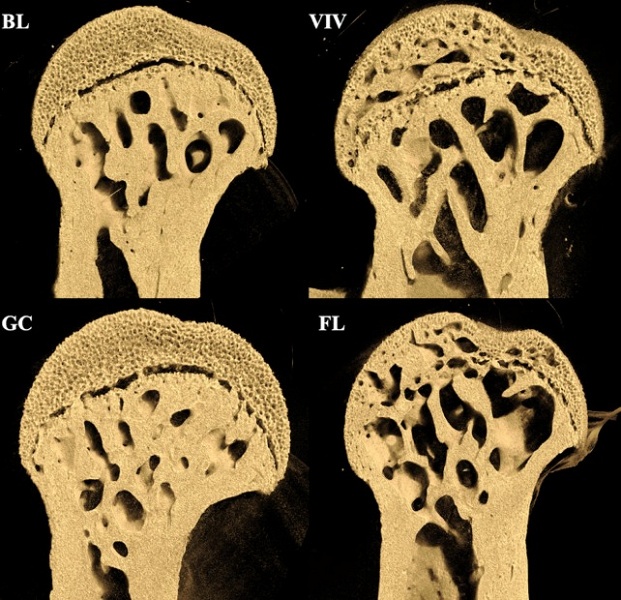

В эксперименте 37 мышей провели месяц на орбите. Анализ их скелетов выявил значительную деградацию в зонах, которые на Земле выполняют несущую функцию. Бедренные кости грызунов, особенно области соединения с тазом и коленом, потеряли до 18% губчатой ткани, в то время как поясничный отдел позвоночника, не участвующий в поддержке веса, остался практически без изменений. Для контроля груШейка бедренной кости наземных контрольных мышей (GC и VIV) и мышей-космонавтов (FL и BL)Шейка бедренной кости наземных контрольных мышей (GC и VIV) и мышей-космонавтов (FL и BL)Шейка бедренной кости наземных контрольных мышей (GC и VIV) и мышей-космонавтов (FL и BL)ппа мышей на Земле прошла симуляцию стресса от запуска, но не подвергалась микрогравитации.

«Если бы радиация или системные факторы доминировали, то мы увидели бы равномерное воздействие на скелет, — поясняют учёные NASA и Blue Marble Space Institute of Science. — Однако разрушение происходит избирательно, концентрируясь в точках, которые в обычных условиях испытывают максимальную нагрузку». Например, шейка бедра, защищённая плотным кортикальным слоем, потеряла до 25% внутренней губчатой структуры — это противоречит теории о влиянии радиации, которая должна воздействовать прежде всего на поверхностные слои.